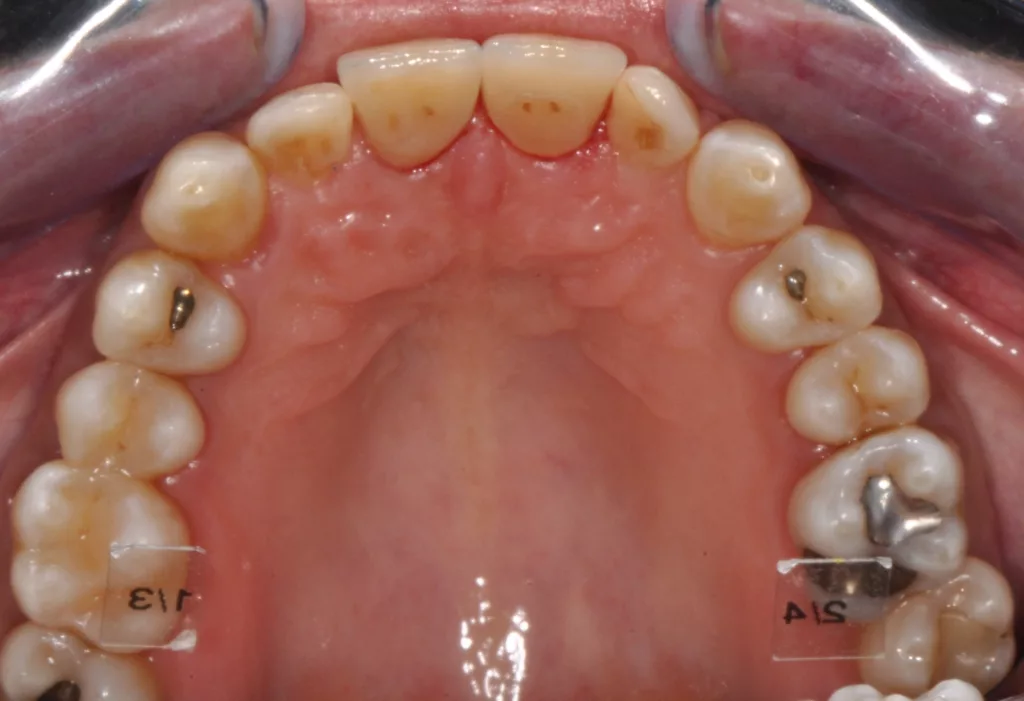

Die 38-jährige Patientin war optisch nicht zufrieden mit ihren Kronen an 11 und 21. Sie entschied sich ebenfalls für eine vollkeramische Neuversorgung. Nach Abnahme der Kronen zeigten sich die Zahnstümpfe moderat verfärbt, weshalb in diesem Fall die Zirkoniumdioxidgerüste CAD/CAM-gestützt aus VITA YZ HT A3 gefertigt wurden, um die bestimmte Grundzahnfarbe schon von innen heraus zu unterstützen (Abb. 10). Die Verblendung erfolgte hier mit der Feinstruktur-Feldspatkeramik VITA VM 9 für Zirkoniumdioxid.